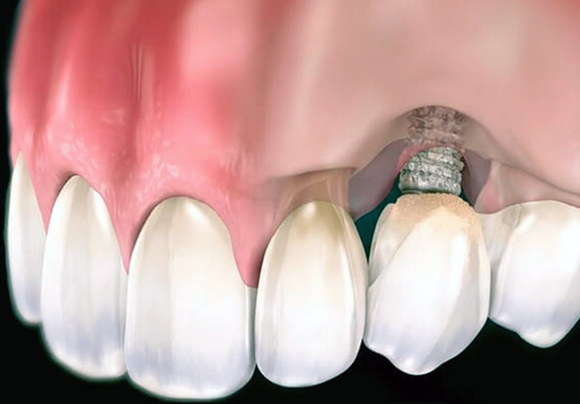

- Наращивание костной ткани биосовместимым материалом, перед этим обязательно проводится удаление патогенных микроорганизмов.

- При отсутствии противопоказаний повторная установка имплантата рекомендуется не позже чем через месяц после извлечения отторгнутого корня. По возможности вживление происходит одновременно с подсадкой костного материала.

- При наличии ограничений установка имплантата растягивается на несколько месяцев. Сначала происходит заживление лунки, затем наращивается объем костной ткани, а после вживляется новый имплантат.